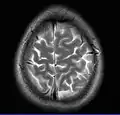

Normal axial T2-weighted MR image of the brain

- T2-weighted (T2W) images: CSF is light, but fat (and thus white matter) is darker than with T1. T2-weighted images are useful for visualizing pathology.[26]